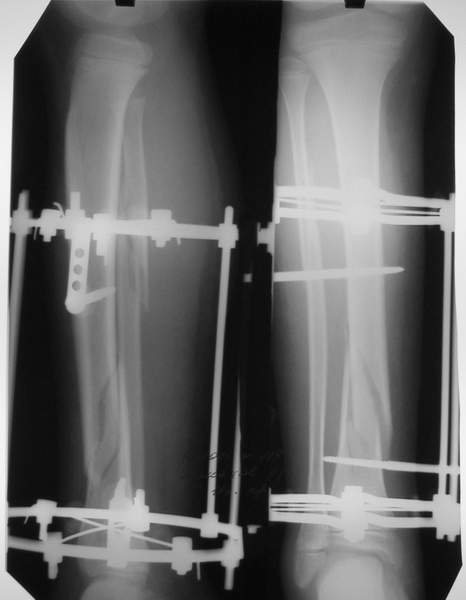

В аттачтах №№ 1 и 2 - примеры, когда 2 кольца не позволили послеоперационно

исправить смещение фрагментов большеберцовой (по ширине и вальгусное).

А казалось бы (#2) - поиграй на штангах и все влетит.

2

3a